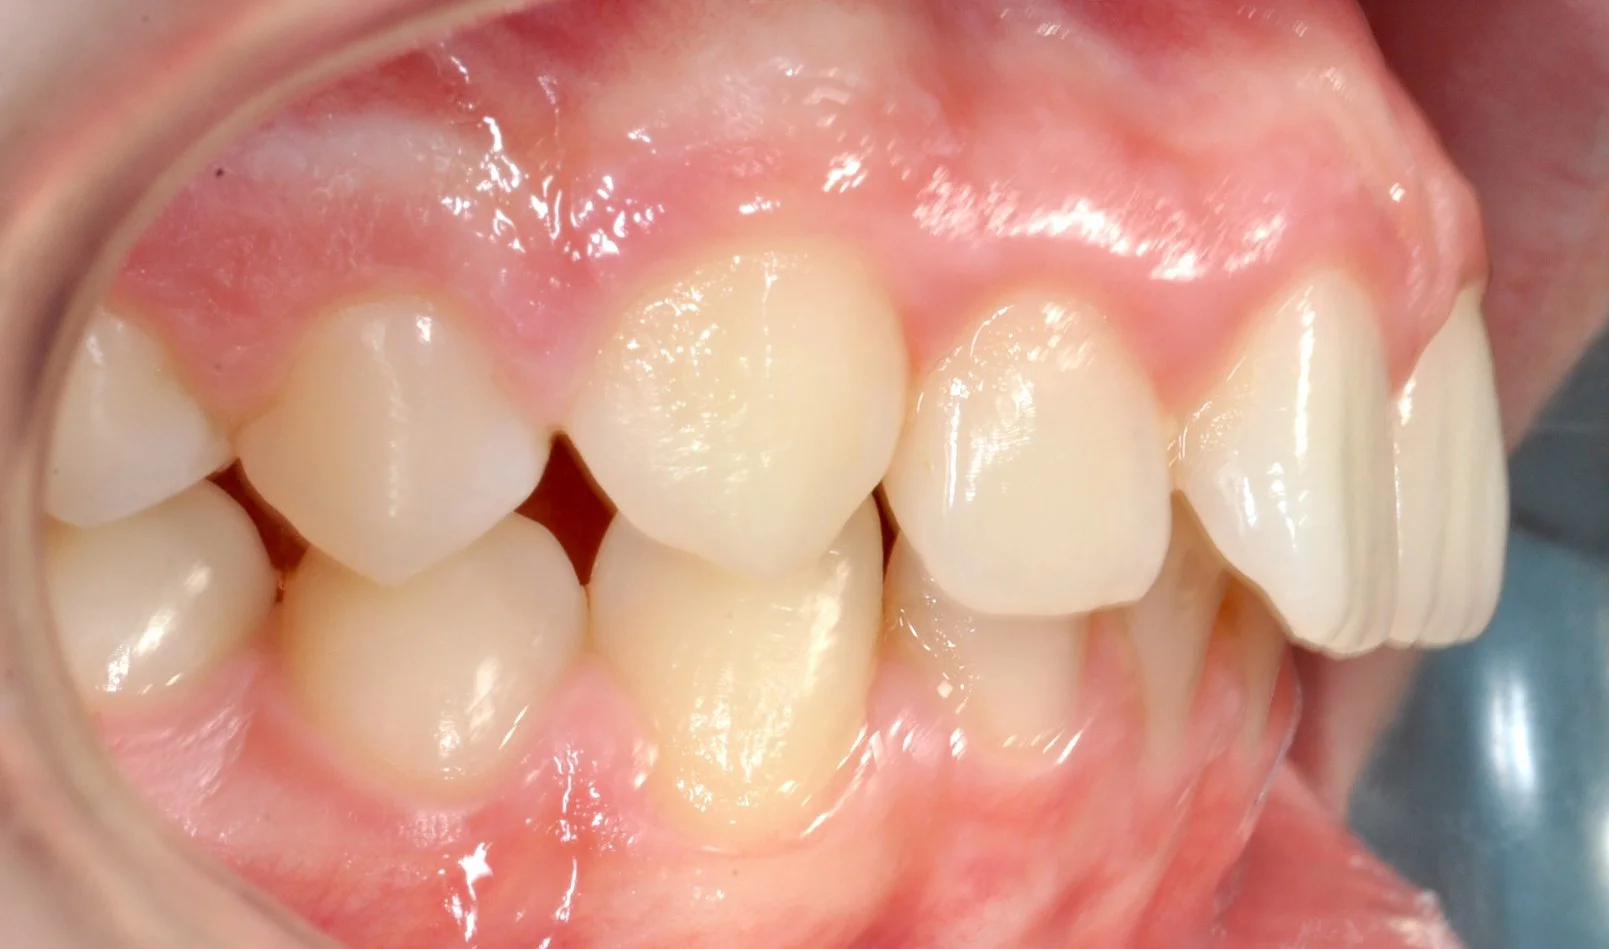

Caso 1 – Allineatori trasparenti in età evolutiva

Giovane paziente in fase di crescita con denti superiori troppo in avanti rispetto agli inferiori, arcate strette e rotazioni importanti di alcuni elementi.

Grazie al trattamento con allineatori trasparenti, in 18 mesi è stato possibile accompagnare la crescita, correggere l’allineamento dei denti e migliorare il rapporto tra le arcate, ottenendo un sorriso più armonioso e funzionale.

PRIMA